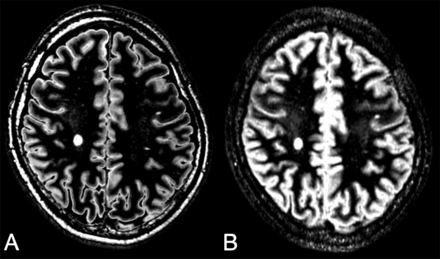

The lesion-to-WM, GM-to-WM, and GM-to-CSF contrasts and their corresponding CNRs of synthetic DIR images were significantly higher than those of conventional DIR images (Table 2 and Fig 6).

Sample sections of synthetic (A) and conventional (B) DIR images. Note the better suppression of WM on the synthetic DIR image.

The quality of DIR images was better in synthetic MR imaging (which was optimized for each patient) than in conventional MR imaging. No previous report has evaluated the image quality of synthetic DIR. Synthetic T1-weighted and T2-weighted images were reported to have higher contrast and comparable CNR compared with conventional images.13 Synthetic FLAIR images were reported to have lower contrast and lower CNR than conventional FLAIR images. In our study, we succeeded in creating synthetic DIR images with higher contrast and CNR than conventional DIR images by optimizing them for each patient. This result shows the potential advantage of synthetic MR imaging, which can be optimized for each patient after image acquisition. A recent report attempted to optimize the DIR image for each patient.25 In this report, DIR images were acquired after obtaining T1 and T2 maps separately and then optimizing the acquisition parameters according to these maps. Because quantification and image creation can be completed in a single acquisition and on the same software, the method used in our study has the potential to reduce the time needed for DIR optimization.